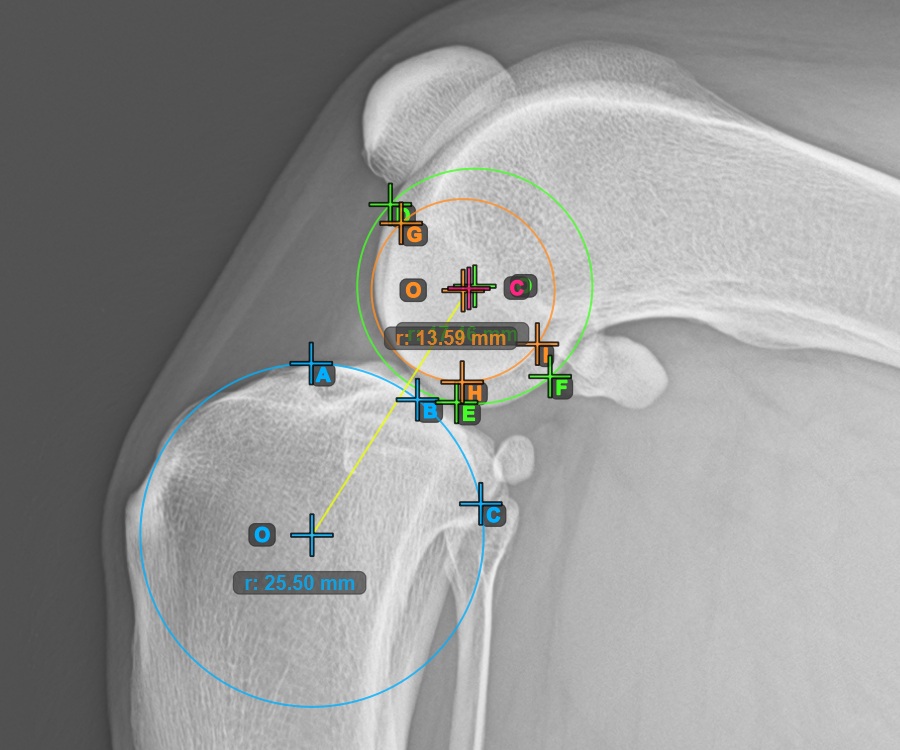

Folytassa a mérést az első Condylus Femoris ízületi felszínén lévő három pont megjelölésével.

Jelölje meg a három pontot a combcsont fő condylusán (Condylus Femoris). A sorrendtől függetlenül ügyeljen arra, hogy megjelölje a legfelső pontot, a legalacsonyabb pontot és a Condylus Femoris középpontját. A három pont alapján a rendszer automatikusan létrehoz egy kört.

A lenti kép az első Condylus Femoris-on elhelyezett három pont tipikus elhelyezkedését ábrázolja.